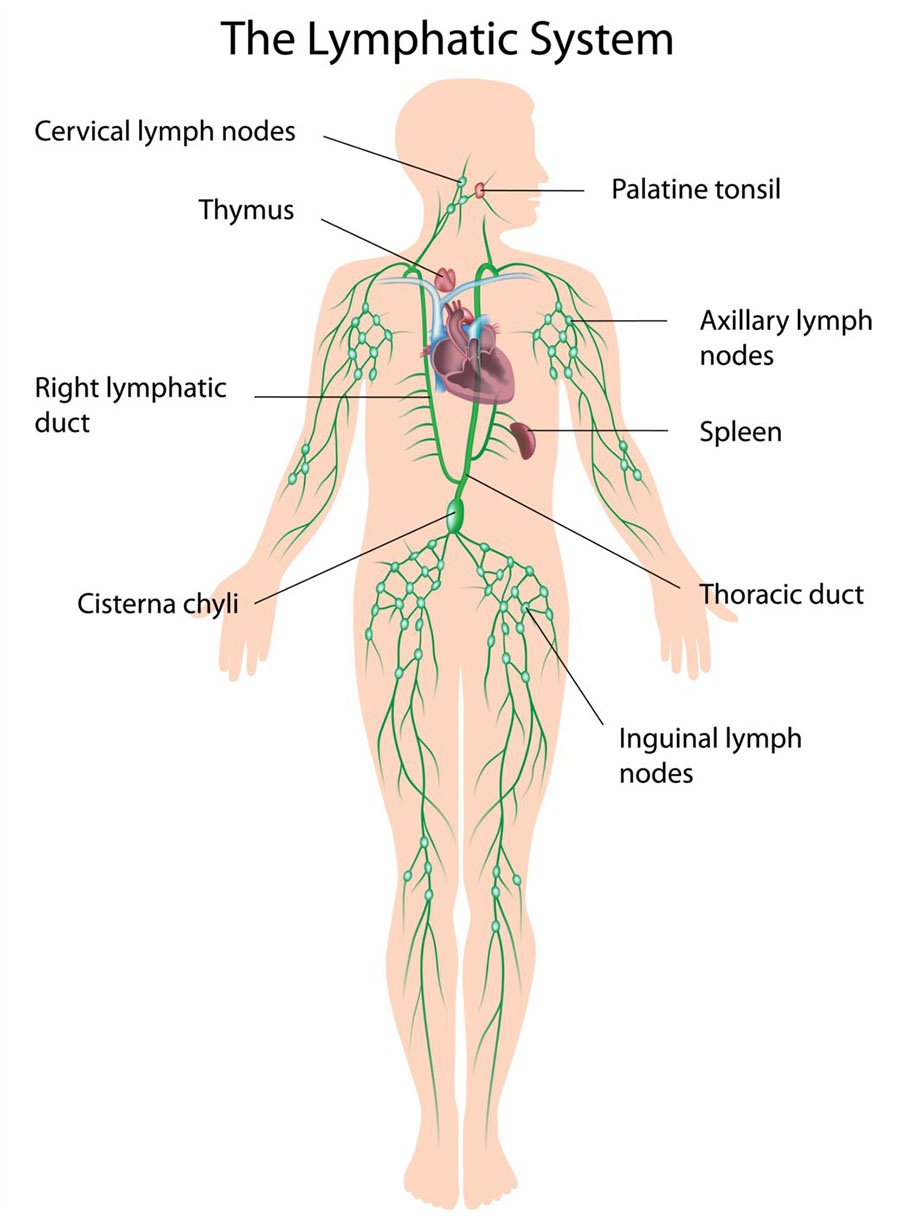

The vaccines invade the lymph nodes and the bloodstream and produce an immune response in those parts of the body. However, the virus itself enters the mucous membrane of the airways. This is the reason why the vaccines only protect against severe disease but do not prevent infection or the transmission of the virus. Only in severe covid-19 cases does the virus pass beyond the membrane of the airways and into the bloodstream - where it has the opportunity to encounter vaccine-induced immunity.

The gene from the mRNA vaccine also invades the lymph nodes and triggers a civil war between the cells that make the spike proteins and the lymphocytes whose job it is to kill cells that make those spike proteins.

Once the mRNA has escaped it can enter the cells of any of the internal organs such as the liver, the spleen and the heart. Once inside these organs the covid-19 vaccine gene will continue to make spike proteins. This will trigger the body’s killer lymphocytes to carpet bomb and destroy those tissues that have spike proteins. This is an auto-immune response. The body starts destroying its own internal organs in order to stop the propagation of the spike proteins.

At the same time, the supply of lymphocytes is eventually reduced because they themselves are fighting their own civil war within the lymph nodes - where the gene for the spike protein has also invaded. Eventually, there is an immune deficiency of lymphocytes. This could have implications for the prevention of tumors. Normally, the lymphocytes will keep the cancerous cells under control and prevent tumors, but if large quantities of lymphocytes are destroyed by the vaccine gene and the autoimmune response to the spike protein, then there will not be enough of them to prevent cancerous cells from propagating.